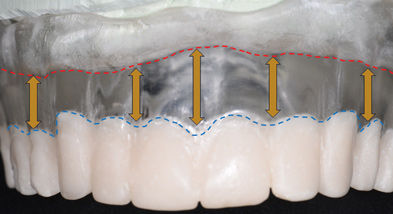

Once the presence or absence of a composite defect has been established, the transition line must be evaluated for patients for whom a maxillary hybrid prosthesis is planned. If a composite defect is present, it would be inappropriate to plan a metal-ceramic or all-ceramic tooth-only restoration because such a restoration would result in esthetic compromises due to longer-than-normal teeth. Therefore, a hybrid prosthesis, ie, a "pink and white" prosthesis, intended to replace the teeth and missing hard and soft tissues should be planned. To maximize the esthetic prosthetic outcome for this group of patients, the transition line between the hybrid prosthesis and the soft tissue of the edentulous maxillary ridge must be clinically evaluated for potential visibility without the maxillary denture in place.

This evaluation can be done by removing the maxillary denture and then having the patient smile (Figure 2). If the soft tissue of the edentulous ridge cannot be seen, the transition between an implant-supported hybrid prosthesis and the residual soft-tissue crest is considered favorable. Conversely, for those patients who do display the residual ridge while smiling, ie, the smile line is apical to the transition line, the transition between a hybrid restoration and the soft tissue will be visible and, therefore, unesthetic. With a visible residual ridge crest, the junction of the artificial gingiva of the hybrid prosthesis and the natural soft tissue will be apparent, and differences in texture and contour between the two may be obvious and unesthetic. However, if the transition line is apical to the smile line, ie, the smile line is incisal to the transition line, a predictable esthetic outcome is possible.

If the crestal soft tissues are visible in the preoperative evaluation, one method to avoid visibility of the transition line in the final hybrid prosthesis is to reduce the residual ridge height to the point where the crest can no longer be seen and is apical to the smile line prior to placement of implants. Thus, an intentional alveoloplasty in conjunction with implant placement would be planned. If ridge reduction is not possible due to large pneumatized maxillary sinuses, the use of a Marius bridge or any variation of an implant-supported overdenture with a flange that overlaps the gingival junction would be indicated.